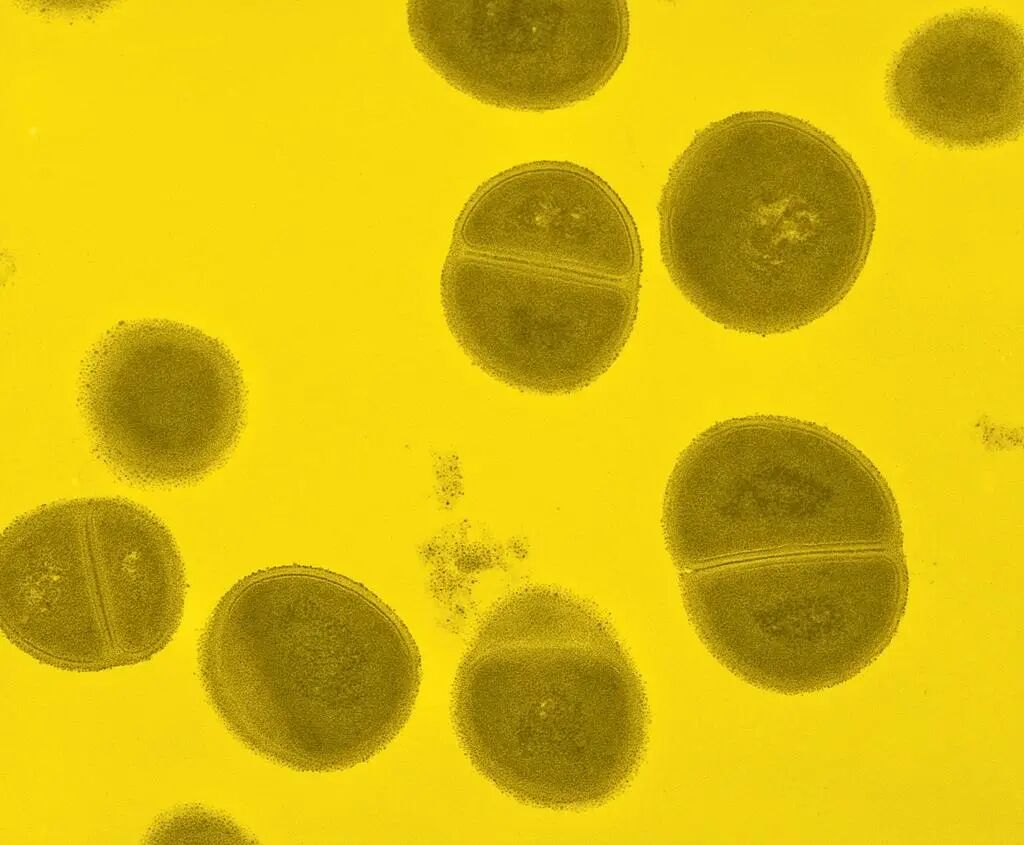

金黄色葡萄球菌

金黄色葡萄球菌是一种广泛分布于自然界中的细菌,其繁殖时会分泌一种特殊毒素——肠毒素。这种毒素耐热性强,即使100℃加热30分钟也无法完全去除,可引发呕吐、腹泻、胃痛等食物中毒症状。

金黄色葡萄球菌,图源:央视新闻客户端